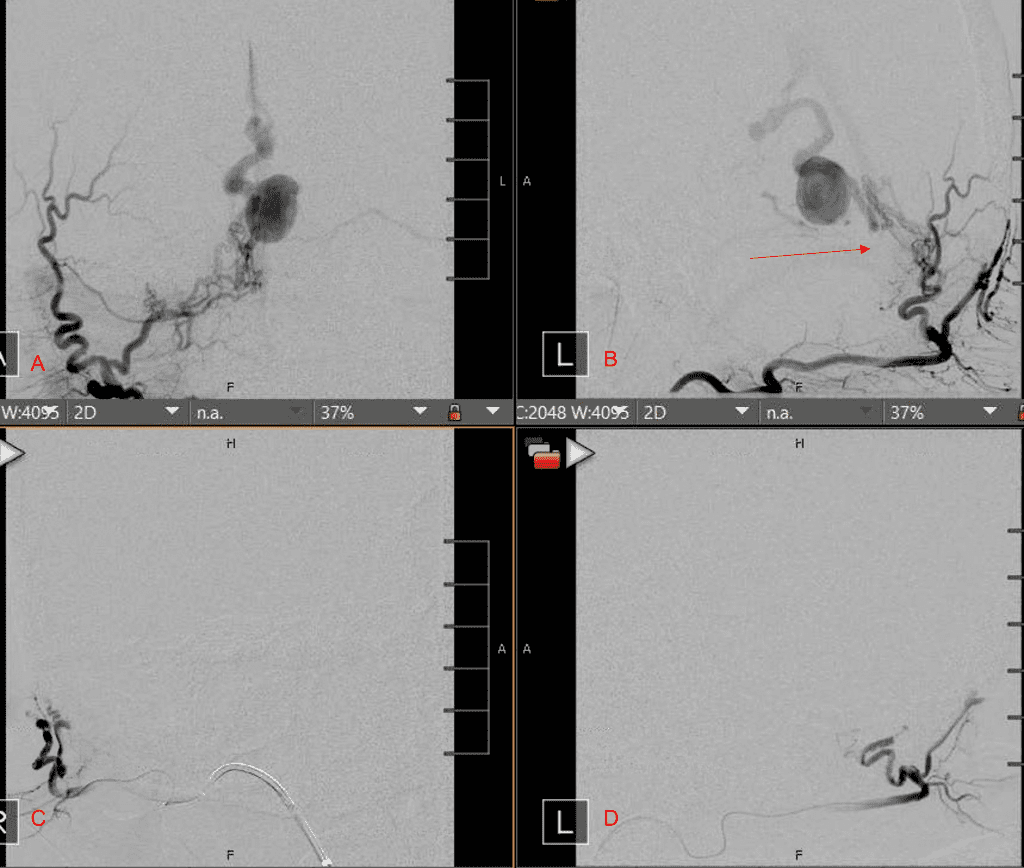

Figure 4. Left ECA AP and Lateral angiograms Pre (A and B) and Post NBCA embolization (C and D) Demonstrate near complete obliteration of Left Occipital Artery Fistulas.